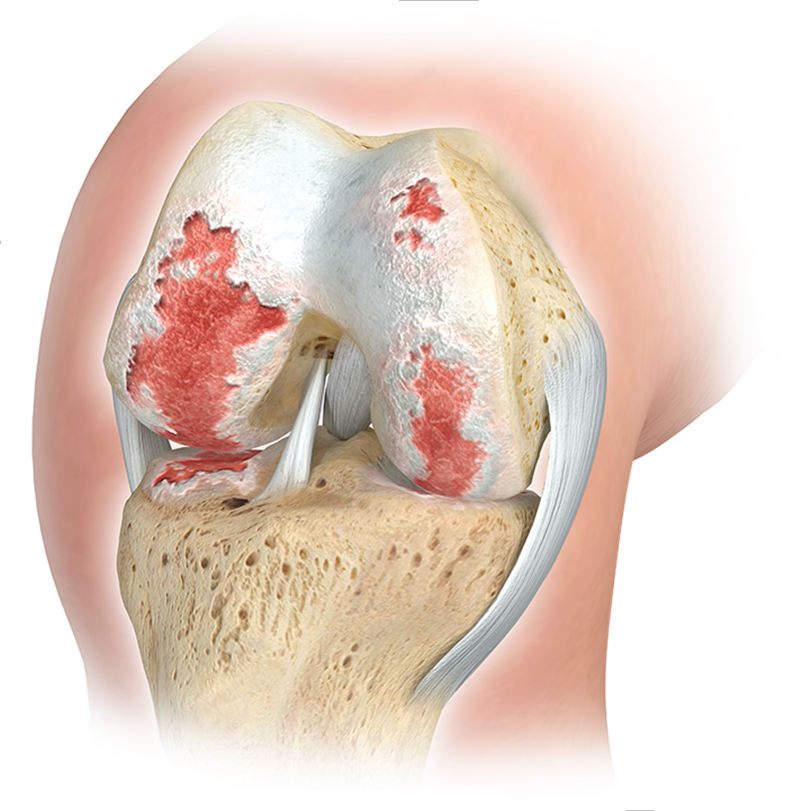

ARTHROSE KNIE

AUF GRUND der Hohen Belastungen, welchen die Kniegelenke ausgesetzt sind, kommt es hier sehr häufig im laufe des Lebens zu Verschleisserscheinungen mit zum deutlichen Beschwerden und Einschränkungen der lebensqualität. frühe sportverletzungen, fehlstellungen oder Übergewicht begünstigen diese entwicklung massgeblich.

IM RAHMEN DER THERAPIE DER KniegelenksARTHROSE (Arthrose Knie) KÖNNEN ZUSÄTZLICH ZU KONSERVATIVEN MASSNAHMEN AUCH CHIRURGISCHE EINGRIFFE NOTWENDIG WERDEN:

- GELENKERHALTENDE OPERATIONEN AM KnieGELENK (KORREKTUR VON FEHLSTELLUNGEN UND ANATOMISCHEN VARIANTEN ZUMEIST MITTELS MINIMAL-INVASIVER GELENKSPIEGELUNG (ARTHROSKOPIE), ZUM TEIL AUCH MITTELS GELENKERÖFFNUNG (MINI-OPEN).

- ENDOPROTHETISCHE OPERATIONEN AM KNIEGELENK (ERSATZ DER ZERSTÖRTEN GELENKANTEILE DURCH KÜNSTLICHE IMPLANTATE AUS Metall und hochvernetztem kunststoff).